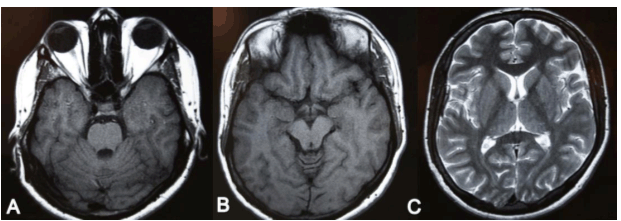

A 22-year-old male patient diagnosed with congestive cardiac failure since age of 18 years presented to emergency service with worsening of the functional class, progressive dyspnea, orthopnea and syncopal episodes. Physical examination revealed jaundice, hypotension, tachycardia, jugular venous distension, hepatojugular reflux sign, rhythmic heart sounds with a mitral murmur, rales in pulmonary bases and painful hepatomegaly. X-ray showed an enlarged cardiac silhouette and bilateral reticulonodulary opacities. Electrocardiography showed signs of dilation of the cardiac cavities. Echocardiographic findings included a severely dilated and hypokinetic left ventricle (ejection fraction less than 10%) and plurivalvular insufficiency without any structural valve damage. Cardiac catheterization confirmed these findings and showed no coronary lesions. Tests for Chaga's disease as well as other infectious and metabolic markers were negative. The patient underwent an uncomplicated cardiac transplantation after three months on waiting list, with an uneventful post-transplantation recovery. During cardiology and cardiovascular surgery follow-up he showed an excellent systolic function (ejection fraction more than 60%), but after six months he complained about gait instability that limited his walking, so he was referred to neurology consultation. After careful history taking the patient acknowledged that since age 15 he had noted a mild lower limb weakness that caused a barely perceptible disturbance in his gait pattern and that in the following years it progressed to gait instability, ataxia, dysmetria and dysarthria. These symptoms had stabilized after transplantation but subsequently worsened in the following months. Upon neurological examination important gait and stance ataxia, dysarthria, lower limb arreflexia and extensor plantar responses were found, as well as pes cavus, hammer toes and mild kyphoscoliosis. This all lead to a clinical diagnosis of FA, confirmed after genetic testing which revealed a homozygous hyper-expansion of 900 and 700 triplets in the frataxin gene. In addition he was diagnosed with Diabetes Mellitus. The patient was lost from neurology consult for the following eight years, during which his ataxia and language disturbance worsened, in spite of keeping an adequate cardiac function. He underwent nerve conduction studies and electromyography, whose results suggested a severe neuropathic pattern (Figure 1C, D). Visual evoked potentials showed disturbances of post-quiasmal visual pathway and the fluorescein angiography showed bilateral optic neuropathy and pigmentary retinopathy in the right eye (Figure 2). Cerebellar atrophy was detected by magnetic resonance imaging (MRI) scans (Figure 3).

Figure 3: Magnetic resonance imaging showing cerebellar atrophy.